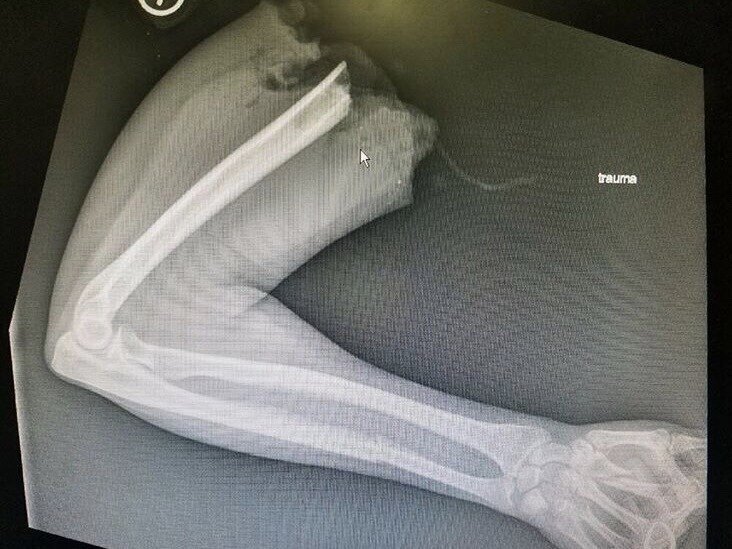

Авария с участием мотоциклистки, которой оторвало руку.